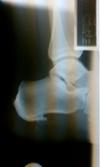

I am going to go through and answer all of these questions and update it every two weeks as i feel there are not enough personal first hand accounts out there. I am including an x-ray also of my foot 3 weeks prior to the surgery.

Recently in April of 2010 at the age of 29 I started getting a bruise on the inner part of my heel. It felt like a bone was coming through the part of my foot. The pain was unbearable at work (I work as a manufacturing associate and stand on concrete full time). An xray showed that I had a calcification form underneath a bone spur. The bone spur was not causing the problem -- the calcification was. After 2 injections, 3 weeks off work, Surgery was decided on.